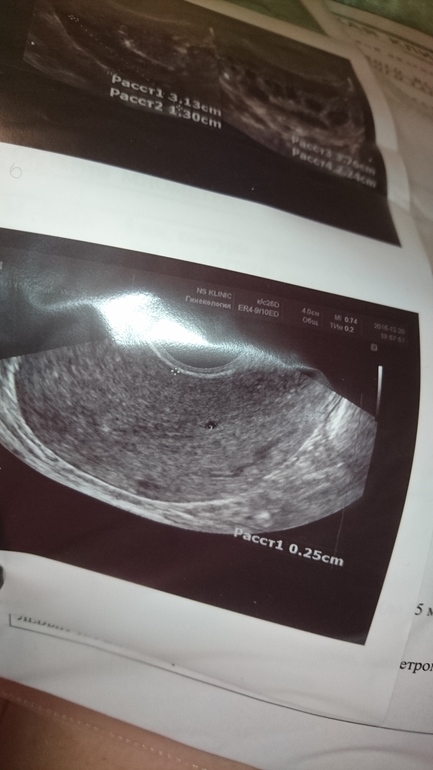

В июле было кесарево, после узи ни разу не делала. позавчера почувствовала внизу живота странные ощущения, даже описать их не могу. Начала переживать что может со швом чтото,ни так заживает и т.д. Пошла на узи, был 21 ДЦ. Врачь диагностировала беременность малых сроков в диаметре 2 мм (под вопросом). тут же пришла домой сделала тест вечерний и он ни чего не показал. следующий сделала утром и на нем слабо проявилась вторая полоска. в этот же день пошла сдала кровь на хгч, пришол результат <1.20 (т.е.не беременна). ни какие гормональные препараты не принимаю и не предохраняюсь.

Хгч отрицательный . Первый тест ничего не показал . На втором видимо реагент . А врач могла и ошибиться . Бывают путают , есть энохогенные включения в эндометрии ( бывает такое ) . У меня так было , врач спутала . После этого я к этому врачу не ходила .

Беременности нет, об этом говорит хгч и пустой тест. Когда на УЗИ хоть что-то могут различить хгч уже в сотнях, людей тест бы показал.